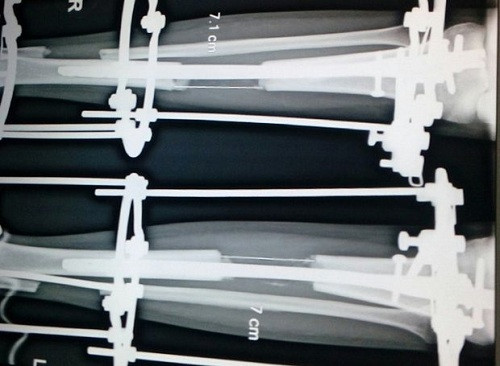

| Hệ thống kéo dài chi lắp trên đôi chân một cô gái Ấn Độ. Ảnh: AP |

Theo Guardian, Komal năm nay 24 tuổi, sống ở Kota, một thành phố miền tây Ấn Độ. Cô tới Delhi năm ngoái để gặp bác sĩ Amar Sarin, một chuyên gia phẫu thuật chỉnh hình đã làm gãy và kéo dài xương chân cho Komal. Cô phải chịu đau đớn hơn nửa năm mới đi lại được.

Cha mẹ Komal phải bán đi phần đất đai tổ tiên để lại cho con gái làm phẫu thuật. Đối với Komal, sự hy sinh này xứng đáng với 8 cm chiều cao.

"Bây giờ tôi tự tin hơn rất nhiều", Komal nói. "Trước đây tôi chỉ cao 137 cm. Người ta thường trêu chọc tôi, còn tôi không tìm được việc làm. Bây giờ em gái tôi cũng đang đi kéo chân".

Người cao lớn được coi là hấp dẫn ở Ấn Độ. Komal là một trong số ngày càng nhiều thanh niên Ấn Độ đi phẫu thuật chỉnh hình để cải thiện hôn nhân và sự nghiệp, khiến ngành công nghiệp phẫu thuật thẩm mỹ nước này bùng nổ.